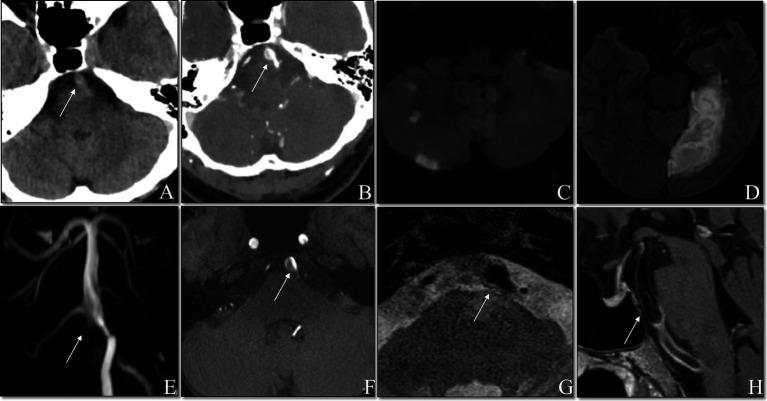

The safety and effectiveness of thrombolysis in patients with intracranial artery dissection (IAD) are still controversial. This study aims to assess the safety and efficacy of intravenous thrombolysis (IVT) in patients with intracranial vertebrobasilar artery dissection (i-VBAD) related acute ischemic stroke (AIS).

A retrospective review of 32 patients admitted to our Neurovascular Center between January 2016 and June 2021 with AIS due to i-VBAD was conducted. Patients were identified and divided into IVT group ( = 8) and non-IVT group ( = 24) receiving standard antithrombotic therapy.

The mean age of the 32 patients was 49.28 ± 15.6 years, with a male predominance (87.5%). All patients presented with clinical manifestations consistent with posterior circulation infarct. Patients in the IVT group were significantly older than those in non-IVT group (58.88 vs. 46.08 years,  = 0.043) and had a higher prevalence of diabetes mellitus (50.0% vs. 8.3%,  = 0.023). No intracranial hemorrhage was observed in of the eight patients in IVT group. An excellent functional outcome, defined as an modified Rankin Scale score of 0-1, was achieved in all eight patients in the IVT group (100%) compared to 15 of the 24 patients in the non-IVT group (62.5%,  = 0.070). Although the difference did not reach statistical significance, the trend suggested a potential benefit of IVT in this patient population.

IVT appears safe with no hemorrhagic complications in i-VBAD patients. It may offer better functional outcomes compared to standard therapy. Larger, prospective, multicenter studies are needed for definitive validation.